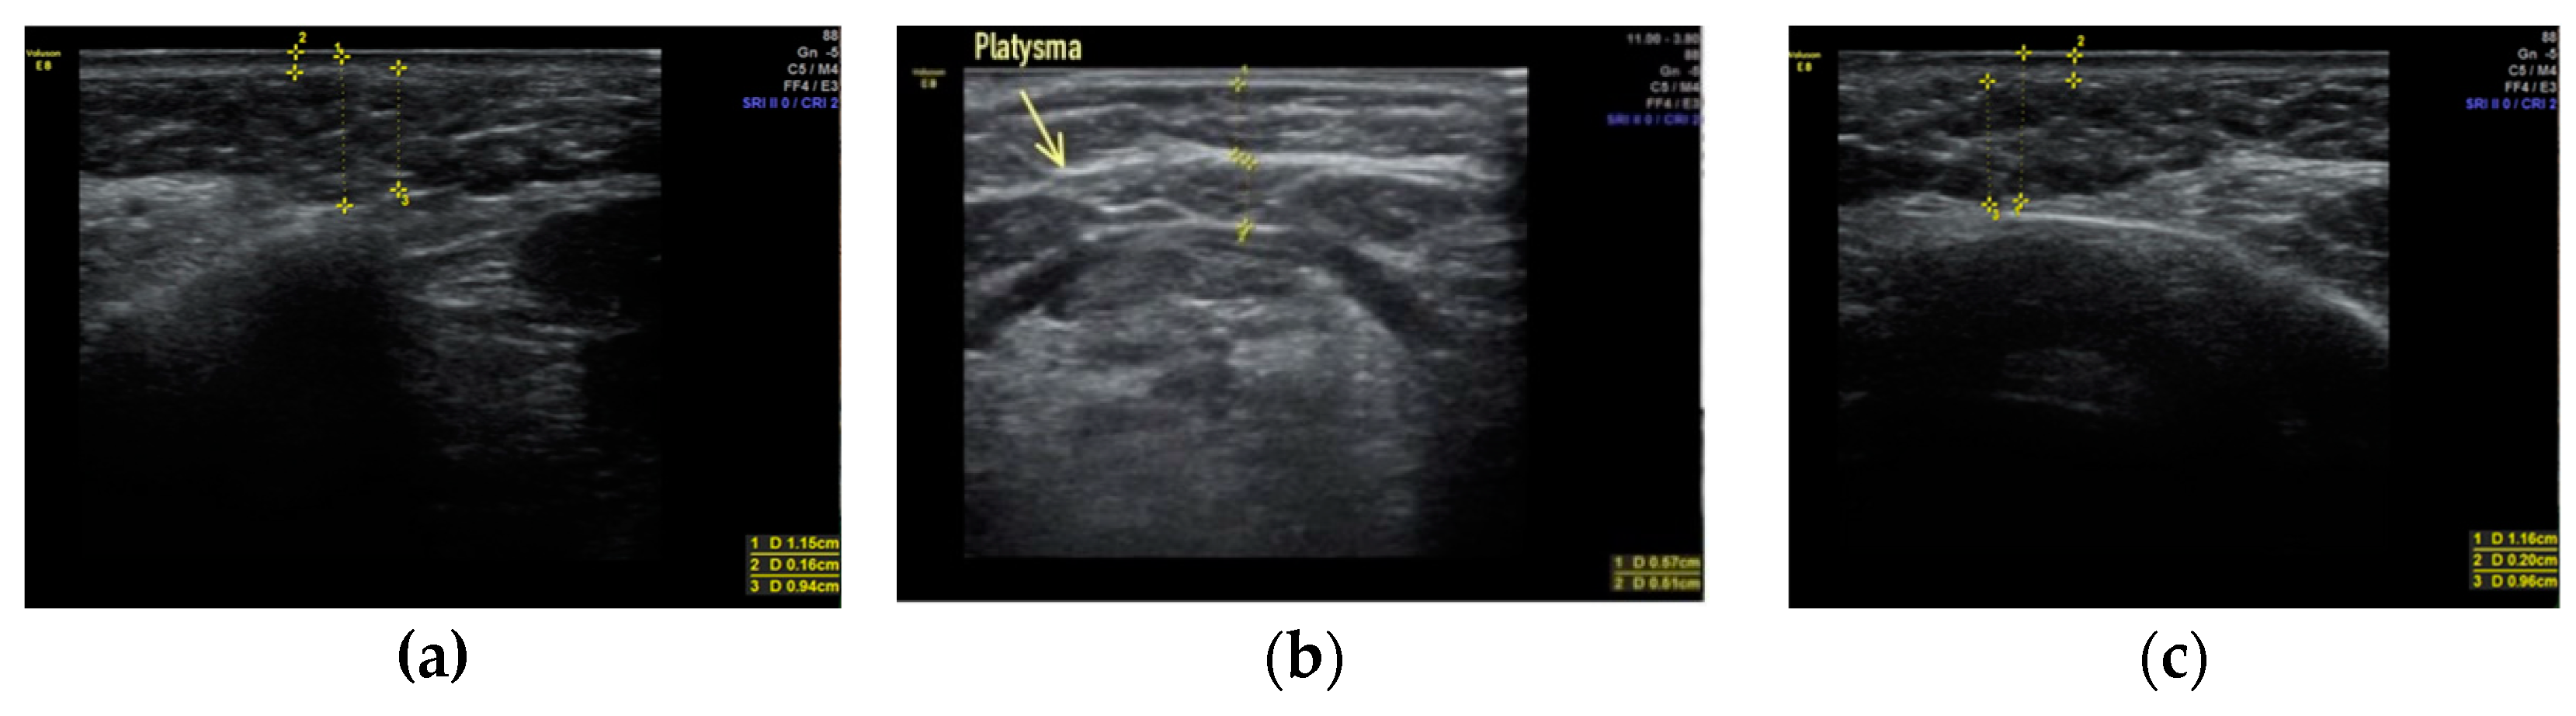

Clinical case #1. During the study, a 43-year-old female patient was examined with a 9 MHz linear transducer of soft tissues of the lower third of the face and neck without pressure, in an upright position; the skin, subcutaneous tissue, and m. platysma were visualized and the degree of their participation in the formation of deformity was estimated. Excessive accumulation of adipose tissue was determined along the contour of the lower jaw from both sides (Figure 1a,c) as well as in the submental area above and below the platysma muscle (Figure 1b).

Figure 1.

B-mode ultrasound examination of the soft tissues of the lower third of the face and neck. A 9 MHz linear transducer. Excessive accumulation of adipose tissue in the submental area, above and below the platysma muscle (b), and along the contour of the lower jaw from both sides (a,c).

Accordingly, it is sufficient to remove this excess adipose tissue by liposuction or lipectomy to correct the contours of the lower third of the face and neck.